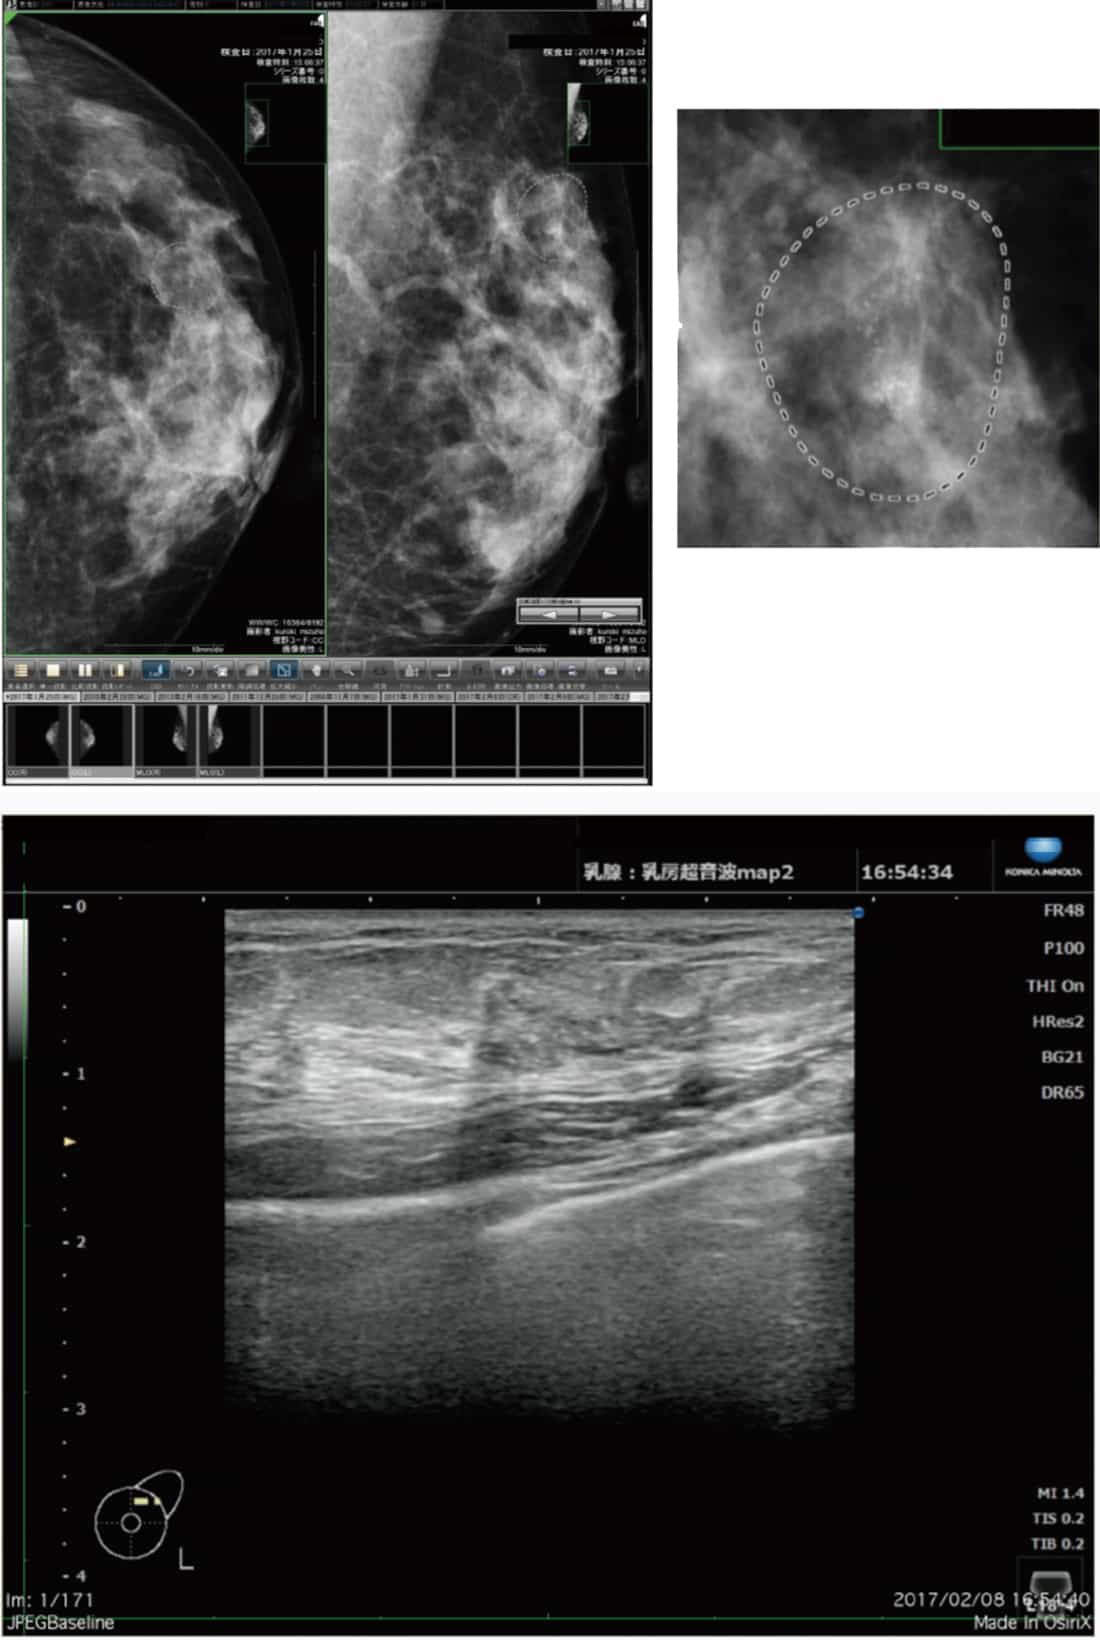

スクリーニングにおけるコニカミノルタの超音波診断装置「SONIMAGE HS1」(以下、HS1)の有用性は、強調差がある点です。 図4の症例は、左U領域にカテゴリー4または5の病変が認められたもので、CADはきちんと指摘しています。 HS1画像では低エコーが強調されて描出されます。小さな硬癌(scirrhous carcinoma)や、radial scar、invasive lobular carcinoma等では、このような強調差があるほうが医師は楽で、技師も見つけやすいです。スクリーニングではこのような強調差のある画像処理は有用であると考えます。 精査における有用性という点では、HS1では23Gの穿刺針の視認性が高く、プローブも小さくて軽いので使いやすいです。 耐久性も評価でき、薬剤などが付着してもビームの切れが少なく、超音波ガイド下での穿刺に適しています。

コニカミノルタのHS1では、石灰化は少しべったりして大きく見えます。慣れないと石灰化に見えないこともあるのですが、慣れれば十分見えてきます。 脂肪の中にある石灰化で、これまで見るのが大変難しかったものも、HS1では良く見えます。図5はカテゴリー4の石灰化が認められる症例です。 CADはしっかり指摘しており、HS1で良く描出されています。

CADはしっかり指摘している(a)。他社の超音画像(b)に比べ、HS1の画像(c)では低エコーが強調されて描出される

このような強調差があるほうが医師は楽で、技師も見つけやすい。

カテゴリー4の石灰化が認められる症例。CADはしっかり指摘しており(a)、HS1で良く描出されている(b)。